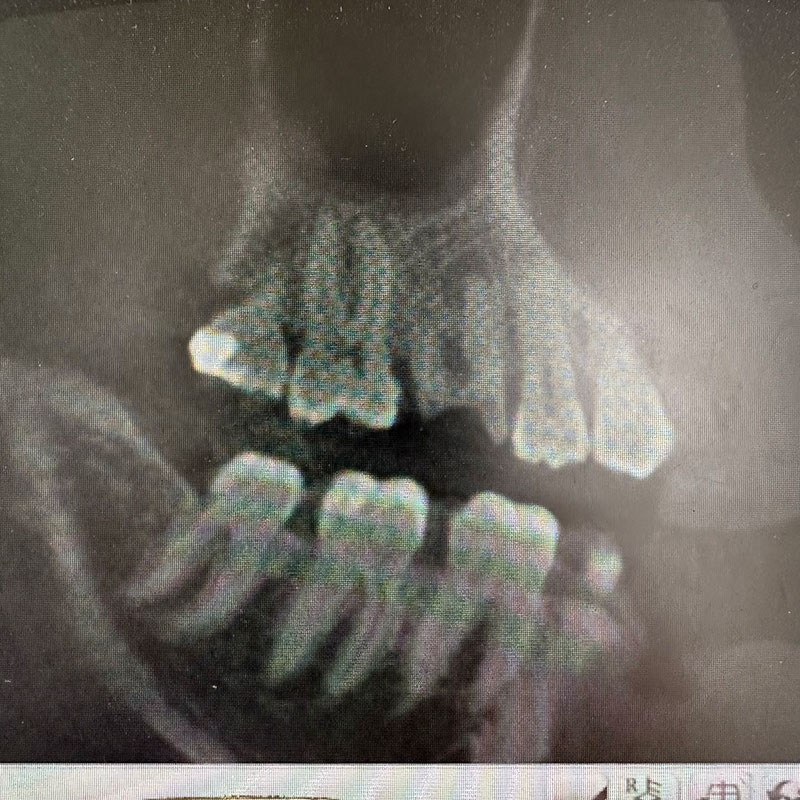

レントゲン写真およびCT画像なのですが、右上6が残歯状態であり歯根破折を起こしている状態でした。しかし歯槽骨から上顎洞底までの距離は十分に認められます。この歯槽骨から上顎洞までの距離がないとソケットリフトなどのオプションの処置が必要になってくるのですが、今回の症例では大掛かりな処置の必要はなく症例の難易度としては比較的イージーな方でした。上顎洞などに関して知りたい方はこちらのページを参照にしていただければと思います。